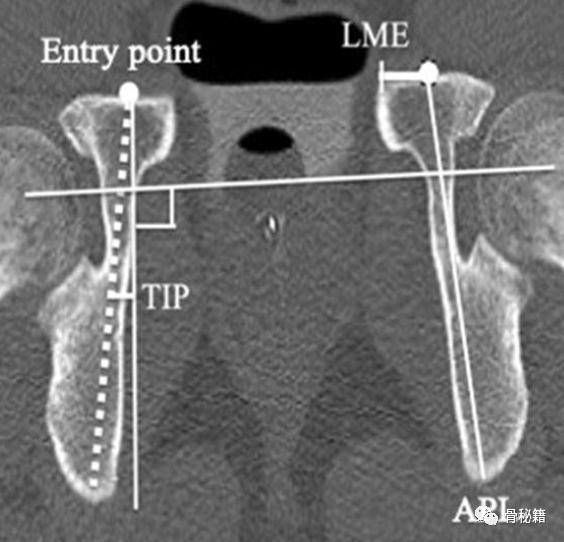

入钉点:理想的入钉点位于髂耻隆起稍偏内。

入钉角度

髋臼内缘的螺钉角度每个人都不太一样

文献研究表示15-45°都有